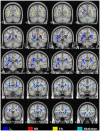

Methods: The biomarker question was addressed in this study by adopting a standardised protocol both for the whole brain (tract-based spatial statistics), and for a region of interest: the midline corpus callosum. In order to study the evolution of tensor changes, cross-sectional data from very mild (N = 21) and mild (N = 22) Alzheimer's disease patients were examined as well as a longitudinal cohort (N = 16) that had been rescanned at 12 months.

Findings and significance: The results revealed that increased axial and mean diffusivity are the first abnormalities to occur and that the first region to develop such significant differences was mesial parietal/splenial white matter; these metrics, however, remained relatively static with advancing disease indicating they are suitable as 'state-specific' markers. In contrast, increased radial diffusivity, and therefore decreased fractional anisotropy-though less detectable early-became increasingly abnormal with disease progression, and, in the splenium of the corpus callosum, correlated significantly with dementia severity; these metrics therefore appear 'stage-specific' and would be ideal for monitoring disease progression. In addition, the cross-sectional and longitudinal analyses showed that the progressive abnormalities in radial diffusivity and fractional anisotropy always occurred in areas that had first shown an increase in axial and mean diffusivity. Given that the former two metrics correlate with dementia severity, but the latter two did not, it would appear that increased axial diffusivity represents an upstream event that precedes neuronal loss.